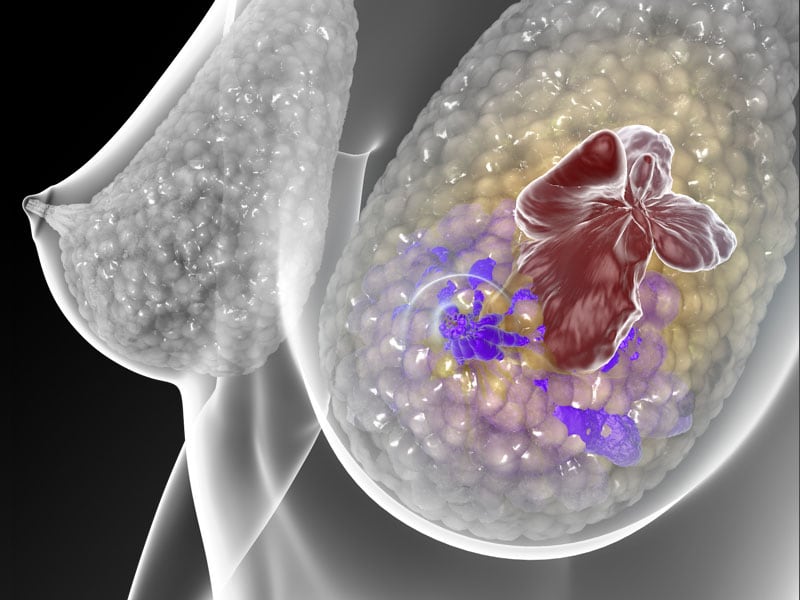

El cáncer de seno es el más común y mortal entre las mujeres en el mundo. Cada año se diagnostican cerca de 1,4 millones de tumores y unas 600.000 mujeres pierden la batalla contra esta enfermedad.

Para la ciencia, es un padecimiento que aún plantea más interrogantes que soluciones; no obstante, la genética parece ofrecer respuestas cada vez más claras para entenderlo y así buscar mejores tratamientos.

Genes, mutaciones, proteínas y hasta la forma en la que se desarrollan los procesos celulares, dan pistas a los científicos.